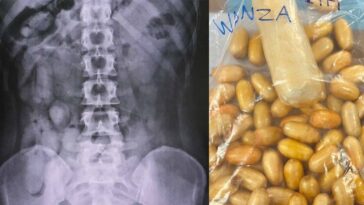

איך נראה קוקאין בתוך הבטן של עצורות בשדה”ת בפוקט